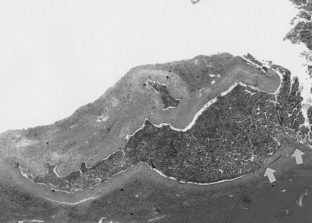

Fig. 4.